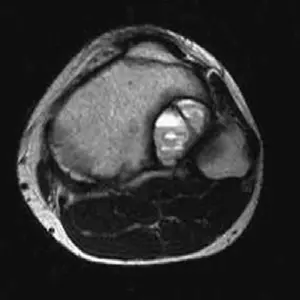

التصوير بالرنين المغناطيسي (MRI)

يُعد التصوير بالرنين المغناطيسي (MRI) هو الفحص التصويري الأكثر حساسية والأفضل لتشخيص كيس العظم المتمدد. يوفر معلومات حيوية لا يمكن الحصول عليها من الأشعة السينية وحدها:

*

مستويات السائل-السائل (Fluid-fluid levels):

هذه هي العلامة المميزة لكيس العظم المتمدد على الرنين المغناطيسي. تظهر كخطوط أفقية داخل التجاويف، تمثل ترسيب مكونات الدم (السائل المصلي، خلايا الدم الحمراء، الفيبرين) بسبب الجاذبية.